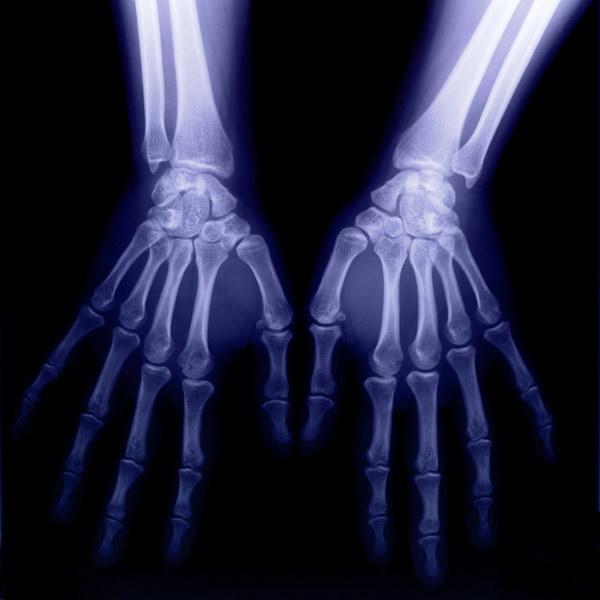

醫(yī)學(xué)領(lǐng)域是X射線技術(shù)應(yīng)用最廣泛的領(lǐng)域。X射線應(yīng)用于醫(yī)學(xué)診斷,主要依據(jù)X射線的穿透作用、差別吸收、感光作用和熒光作用。由于X射線穿過人體時,受到不同程度的吸收,如骨骼吸收的X射線量比肌肉吸收的量要多,那么通過人體后的X射線量就不一樣,這樣便攜帶了人體各部密度分布的信息,在熒光屏上或攝影膠片上引起的熒光作用或感光作用的強弱就有較大差別,因而在熒光屏上或攝影膠片上(經(jīng)過顯影、定影)將顯示出不同密度的陰影。根據(jù)陰影濃淡的對比,結(jié)合臨床表現(xiàn)、化驗結(jié)果和病理診斷,即可判斷人體某一部分是否正常。于是,X射線診斷技術(shù)便成了世界上最早應(yīng)用的非刨傷性的內(nèi)臟檢查技術(shù)。

X射線應(yīng)用于治療,主要依據(jù)其生物效應(yīng),應(yīng)用不同能量的X射線對人體病灶部分的細胞組織進行照射時,即可使被照射的細胞組織受到破壞或抑制,從而達到對某些疾病,特別是腫瘤的治療目的。

X射線照射下的手掌影像圖